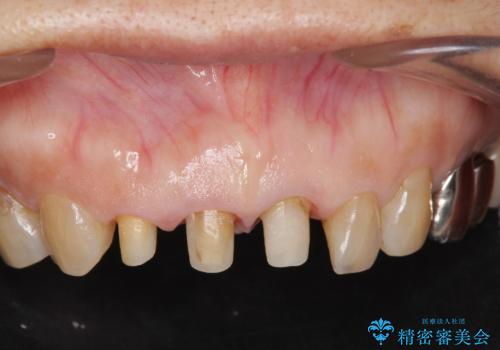

前歯の審美改善

- 孫娘の結婚式に合わせて前歯を綺麗にして写真映りをよくしたいと来院されました。

結婚式に合わせて根管治療からのやりかえを短期集中治療で計4回で終える計画を立てます。

セラミック治療は外から見えるのはクラウンの色味・形態、歯肉の状態のみですが、X線撮影において現れるクラウンと歯牙の適合や、ファイバーコアの精度・根管充填の密度に、より長い予後を達成するための要素が含まれると考えます。